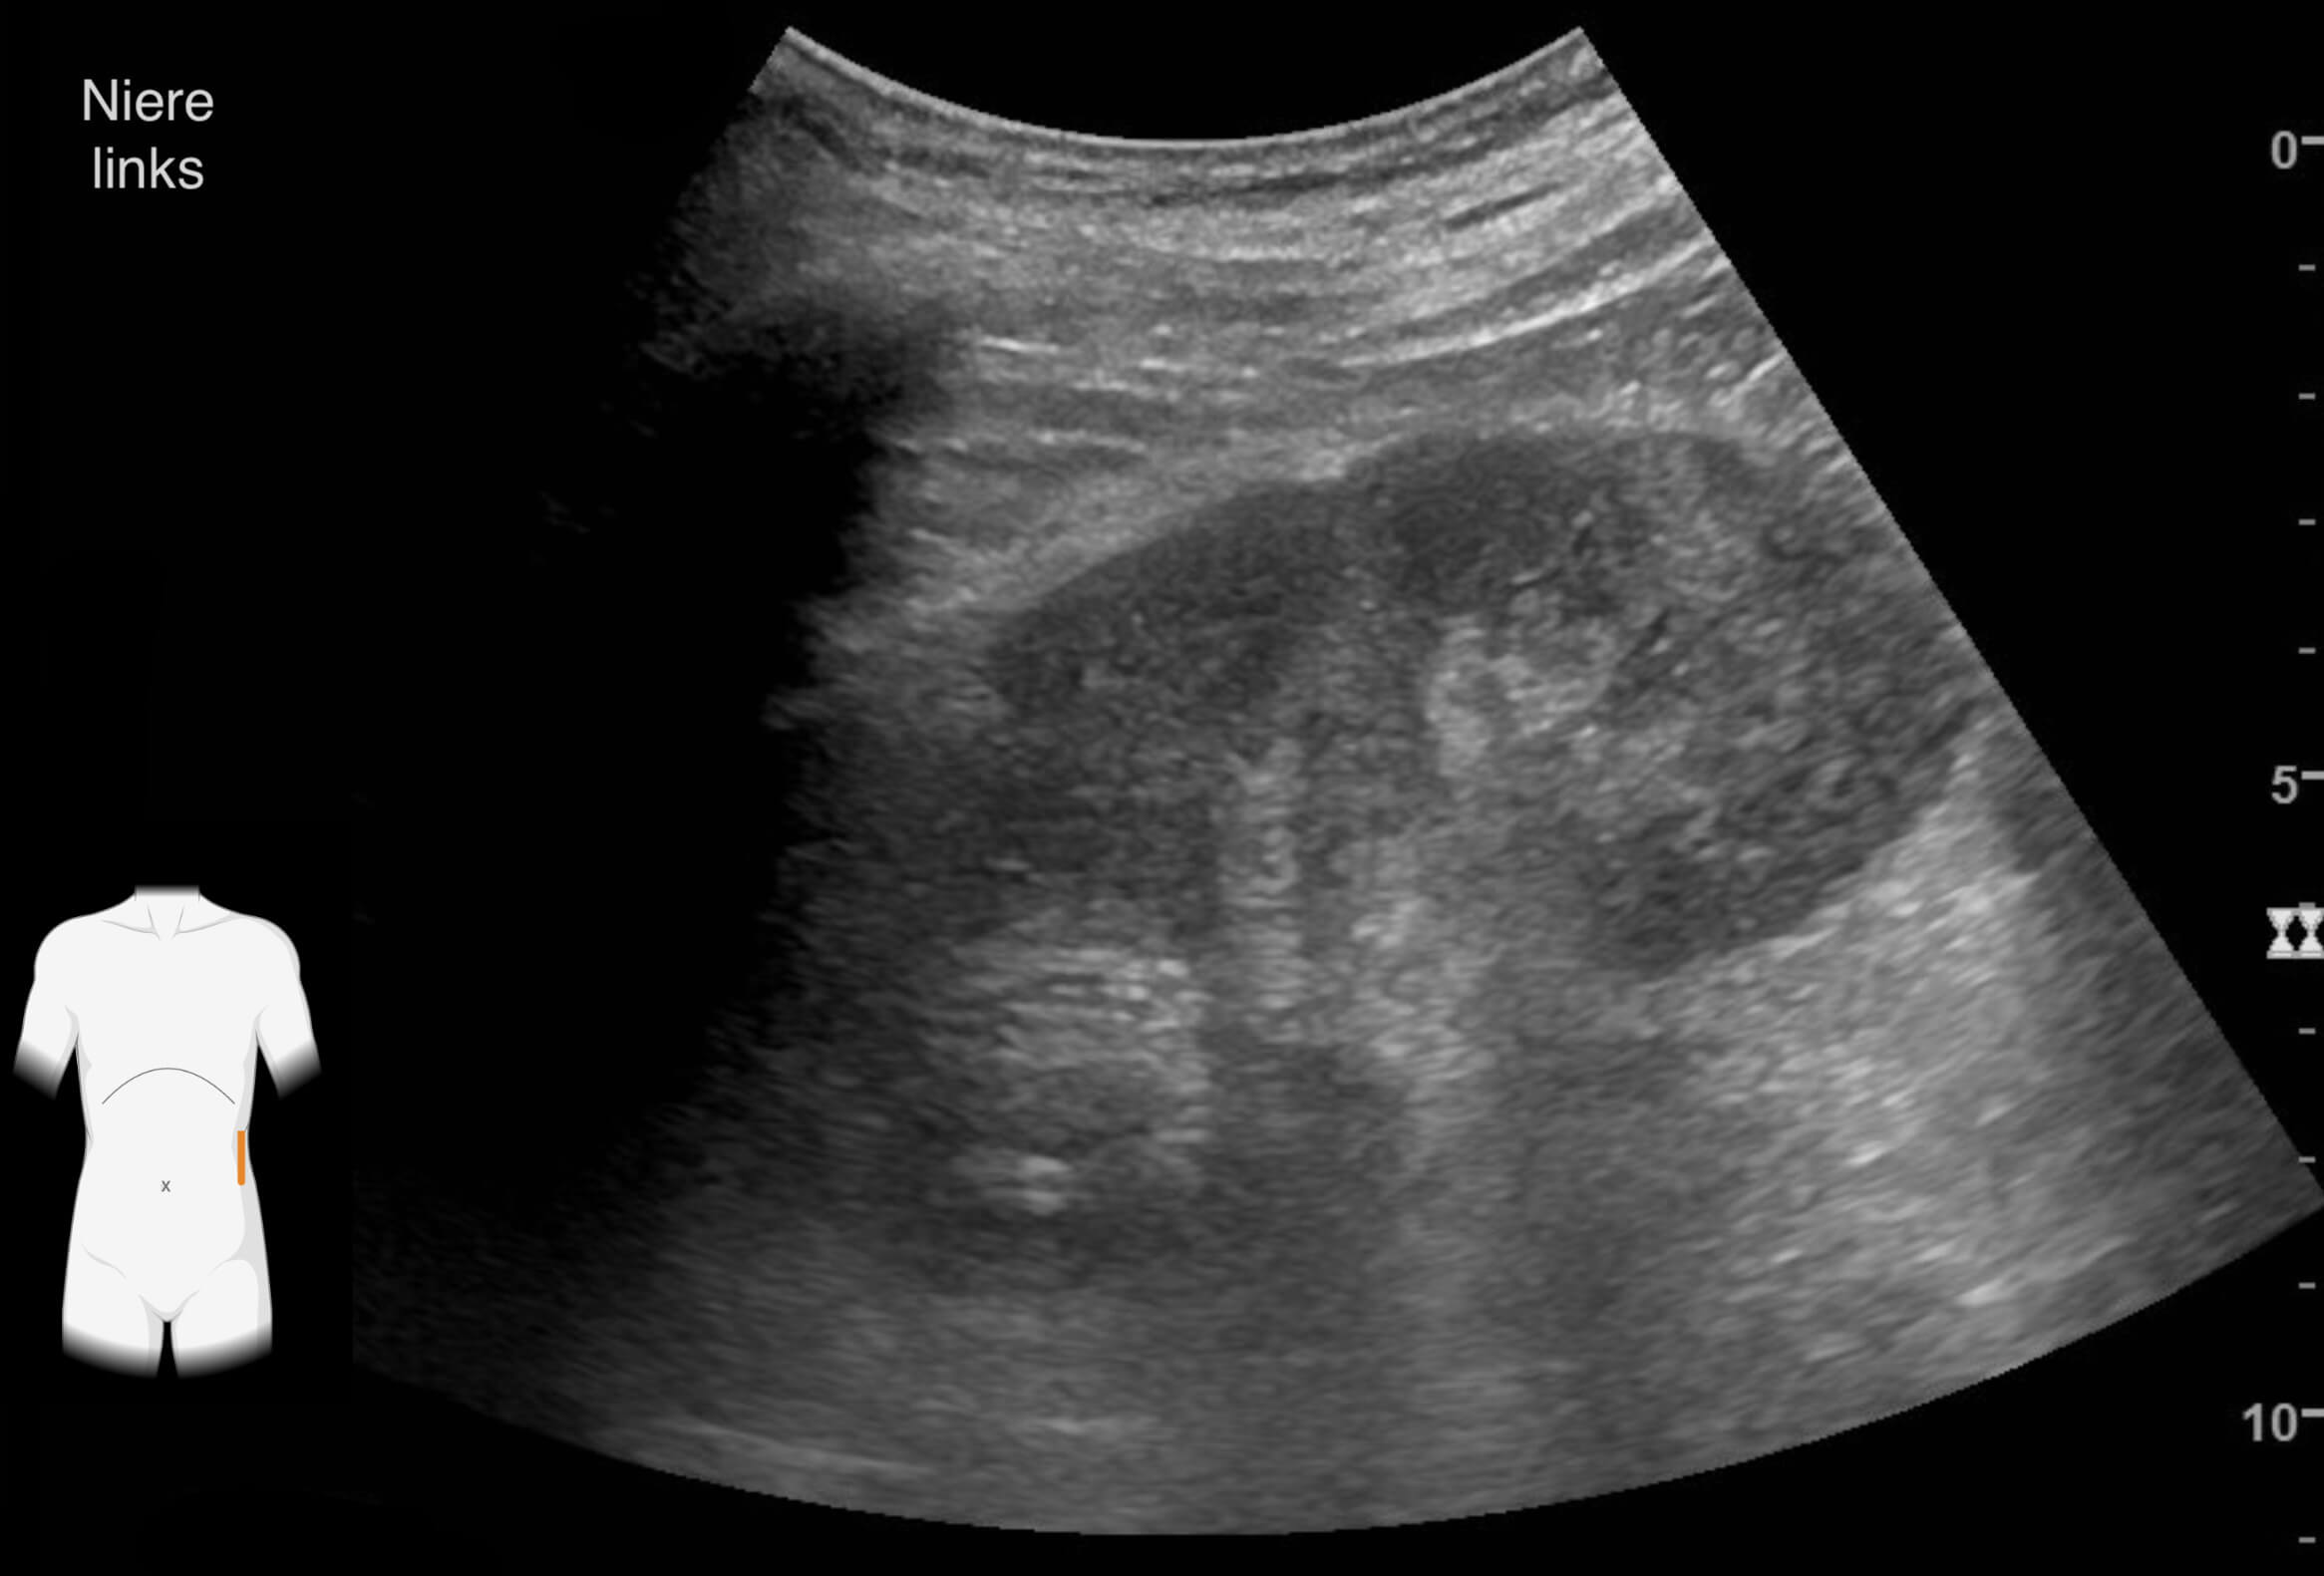

Die Ergebnisse der durchgeführten Untersuchungen kannst du dir hier anschauen:

Die Befunde geben eindeutige Hinweise auf die Erkrankung von Frau Lorenz. Wie bewertest du die Ergebnisse?